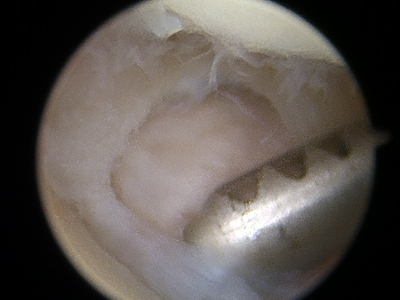

Minimally Invasive Arthroscopy – Small incisions (less than 1cm) for faster recovery and minimal scarring

Common Procedures – Carpal tunnel release. De Quervain's release. TFCC repair. fracture fixation. ulnar shortening osteotomy. etc.